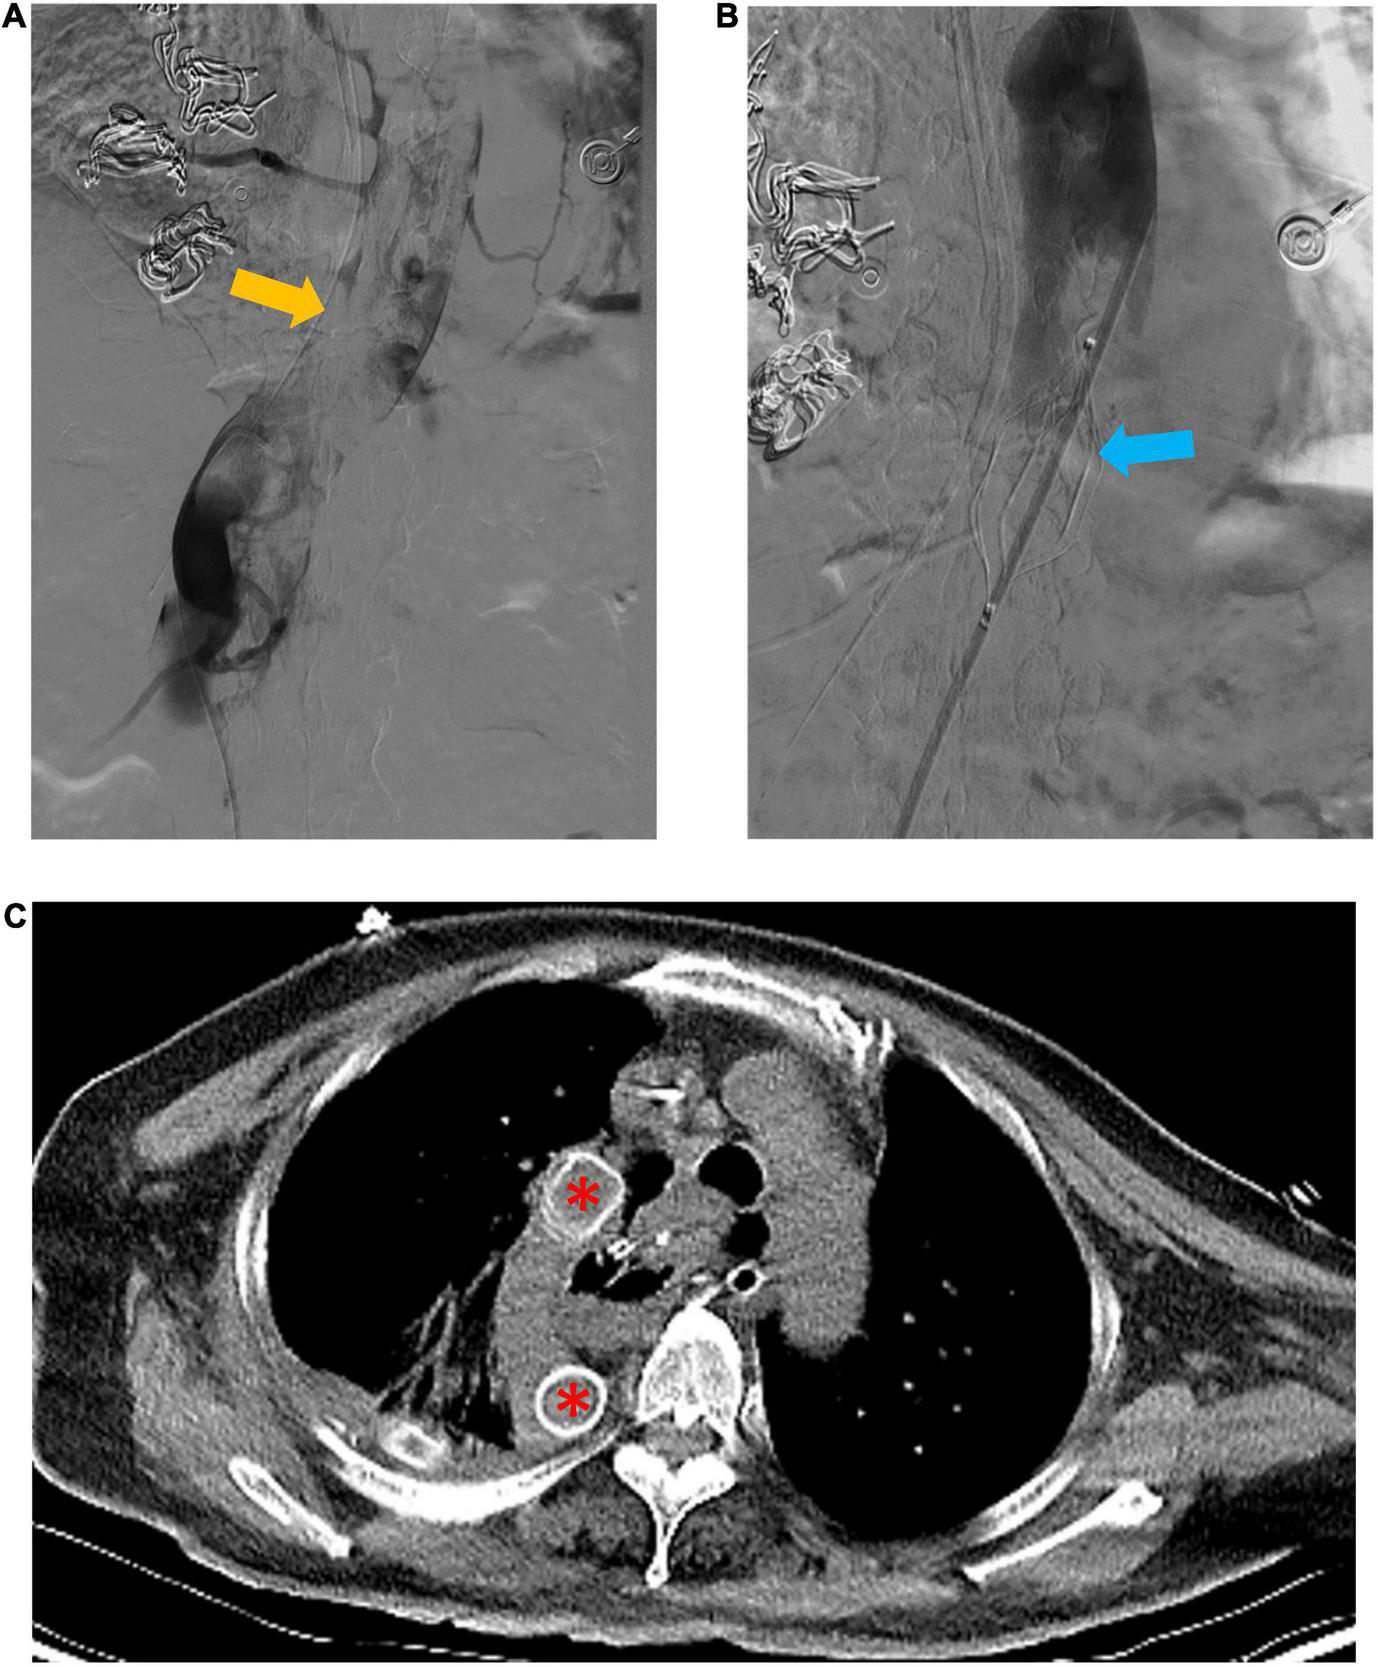

An emergency digital subtraction angiography (DSA) of the inferior vena cava and double renal vein was performed 24 h post-operation. Angiography demonstrated a large thrombus at the azygos vein from the level of the diaphragm to the level where it was divided during surgery (Figure 2A). The patient underwent a thrombectomy and the placement of an inferior vena cava filter above the bilateral renal vein (Figure 2B). Artificial vascular bypass grafting was used to further reconstruct the venous drainage: the proximal part was anastomosed to the right atrium, and the distal end of the graft was anastomosed to the azygos vein at the level where it was divided during surgery. The artificial vessel was easily located on the postoperative routine CT evaluation (Figure 2C) (April 3, 2021). Unfortunately, the patient remained anuric after surgery, and continuous renal replacement therapy (CRRT) was used to provide renal support.

FIGURE 2

Emergency digital subtraction angiography (DSA) of the inferior vena cava and artificial vascular bypass to reconstruct venous drainage. (A) Shows a large thrombus (yellow arrow) in the azygos vein. (B) Shows the inferior vena cava filter (blue arrow) superior to the bilateral renal vein. (C) Shows the well-located artificial vessel (red asterisk).